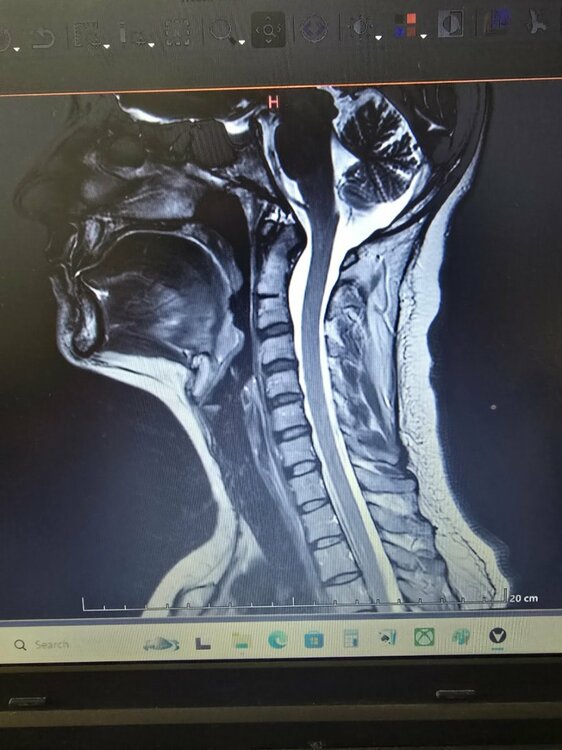

Здравствуйте. Я внимательно посмотрела ваши снимки и описание. Вы уже проделали большую работу — прошли операцию, несколько специалистов и целый комплекс обследований. По МРТ головного и спинного мозга ничего угрожающего нет. Опухолевых или сосудистых изменений не обнаружено. Небольшой «сиринкс» в шейном отделе — это, скорее всего, лёгкое расширение центрального канала спинного мозга. Подобные находки встречаются нередко и чаще всего не несут опасности. Их просто наблюдают раз в год-два, чтобы убедиться, что они не увеличиваются. Поводов для паники нет. Во-вторых, ваши жалобы — чувство «окаменения» головы, боли в шее, тяжесть, головные боли — могут быть связаны с мышечно-тоническим напряжением в шейно-затылочной зоне, которое нередко возникает на фоне остеохондроза, стрессов и гормональных перестроек (в том числе после удаления щитовидной железы). Такие ощущения могут быть очень выраженными и мешать нормальной жизни, хотя причина чаще функциональная, а не структурная. Что сейчас целесообразно сделать: Проверить уровень ТТГ, свободного Т4, кальция и витамина D. После удаления щитовидки важно держать гормональный баланс под контролем. Даже небольшое отклонение может вызывать утомляемость, тревогу, мышечные спазмы и колебания настроения. Сдать ферритин и витамин B12. Дефициты этих веществ часто вызывают слабость, головокружение и ощущение «тумана» в голове. Разобраться с лимфоузлами. Реактивное увеличение до 15 мм на фоне частых воспалений — это чаще следствие хронических очагов (например, миндалин или пазух). Стоит сделать общий анализ крови, С-реактивный белок и обратиться к ЛОР-врачу, чтобы исключить затянувшуюся инфекцию. Для шейного отдела: подойдёт курс мягкой физиотерапии — магнитотерапия, электростимуляция, лечебная гимнастика, релаксирующий массаж. Иногда добавляют препараты с магнием или миорелаксанты, но это решается очно с неврологом. Избегайте агрессивных мануальных воздействий. После операции на щитовидке и при шейных изменениях любые резкие манипуляции противопоказаны. Лучше работать с реабилитологом, который владеет мягкими техниками. Психоэмоциональный компонент. После пережитой операции и постоянных обследований нервная система часто находится в повышенном напряжении. Это естественно. Здесь помогают дыхательные техники, прогулки, нормализация сна и, если необходимо, курс мягких седативных средств по назначению врача. В целом ситуация контролируемая. Сейчас важно не искать у себя опасную болезнь, а постепенно восстанавливать баланс — гормональный, мышечный и эмоциональный. Если хотите, я помогу вам составить поэтапный план восстановления — с обследованиями, питанием, физической активностью и поддерживающими методами. Хотите, чтобы я сделал такой план? ⚠ Важно: Согласно законодательству РФ (ст. 70 Федерального закона № 323-ФЗ «Об основах охраны здоровья граждан в Российской Федерации»), назначение лекарственных препаратов возможно только после очного осмотра врача и установления диагноза. Поэтому приведённые рекомендации не являются индивидуальным назначением, а представляют собой обобщённые терапевтические подходы, применяемые в аналогичных клинических ситуациях. Для точного подбора терапии и исключения противопоказаний необходимо обратиться к врачу очно.

Добрый день всем. Мне 37 лет. 1 года назад удалили щитовидку. По показания (фоликулярный неоплазия, оказалось аденомой). После этого у меня постоянно выполнение лимфатических узлов, и гнойные инфекции они и раньше были.1 недели опухают потом отпускают и опять заново, Я пошла на узи там 2.2см. Отправили к Орл, пока дошла очередь лимфатические узлы уменьшились. Тот отправил делать Мрт. (На Мрт шейного отдела, лимфо узлы 15 млм, и Диски позвонков ранние дегенервтивные изменения, и маленький сиринкс позвонка Т2. Других аномалий не нашли. Головные боли усилилисьи постояннов сердце екала . Я уже к неврологу за таблетки тот прописал успоительные, (то я кажусь ему в стрессе) и отправил меня уже на энцефелограму, там А ритм 8-9 Гц нестабилен, и Интерференция периодических медленных θ -волн без явных очагов. Потом отправил меня к Неурохирургу, тот дал направление на Мрт головы. На мрт головы всё чисто ничего не нашли. У меня голова как будто замороженная, или твердеет окаменеет, даже не знаю как объяснить. Периодически боли с передней шеи где постоянно чувствую там то ли гланды болят какие-то то-ли лимфо...и задняя часть шею болит тоже. Массаж, холодный душ, киропрактик помогает временно. Вес у меня 70кг при росте 159 см. Занимаюсь ходьбой